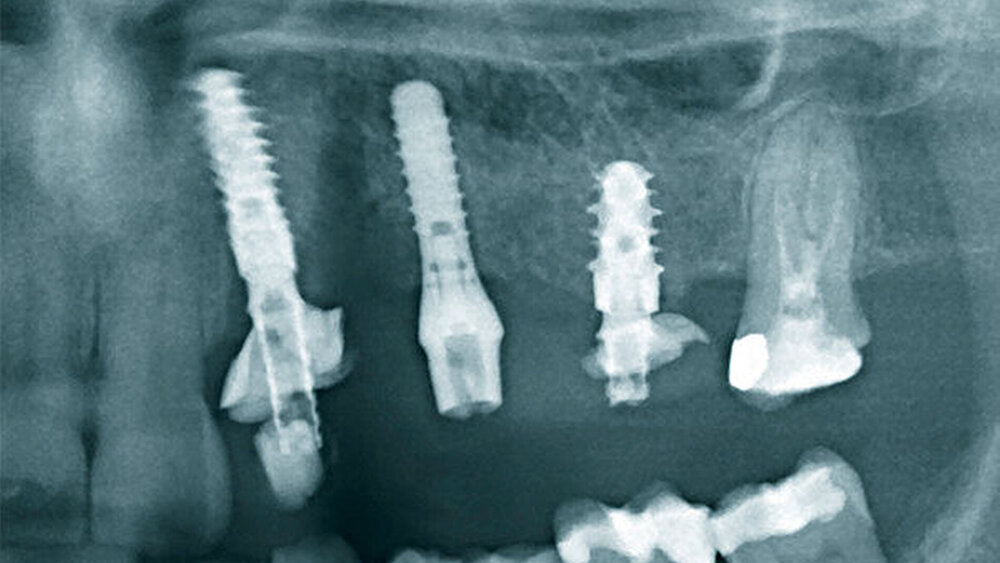

Schnutenhaus:

Wir haben extrahiert, dann die Implantate inseriert, direkt nach der Implantation die Scanbodys aufgesetzt, den optischen Abdruck genommen und das Langzeitprovisorium aus PMMA verschraubt. Dass die Innenverbindung immer die gleiche ist, hilft dabei sehr. Eine Prothetik passt tatsächlich auf alle Implantate.